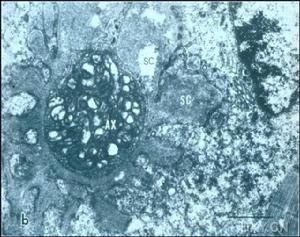

進行性系統性硬化症(1)動脈組織學改變:PSS患者腎血管組織學改變的主要病變部位在小葉間動脈和小動脈。血管病變可分為急性和慢性。急性血管病變有以下兩種類型:一種為內膜增殖呈黏液水腫樣,該類型主要影響較大的動脈。另一種為纖維素樣壞死,主要影響小動脈。這些病變可能是局灶性的,也可能是全身性的。

①急性期:黏液水腫性內膜增殖首先出現在小葉間動脈,少數出現於小弓形動脈,大弓形動脈和葉間動脈常不被累及。血管受累的典型病變為同心圓狀黏液水腫性內膜增生,細胞相對少見,管腔變狹窄。內皮細胞水腫,局部脫落,內膜基質鬆散,蘇木精-嗜伊紅染色基質呈輕度嗜鹼性或透明,三色染色黏液樣基質呈透明或淡藍色。基質中存在少量拉長的肌內膜細胞,這些細胞呈螺鏇式同心圓狀排列,即所謂“洋蔥皮”樣結構。有些動脈黏液樣基質內含有嗜鹼性粒細胞、嗜品紅的小簇纖維蛋白樣物質,這些物質對纖維蛋白染色呈陽性反應。數量不等的纖維蛋白沉積在狹窄的管腔,狹窄的管腔常充斥淤積的紅細胞,碎片紅細胞沉積在深層內膜基質,這為微血管病性溶血性貧血參與本病發病機制提供了形態學依據。血管中層變薄擴展,圍繞擴張的內膜,血管外徑增加,三色染色法顯示血管中層輕度硬化。外膜改變不明顯,有些可觀察到外膜輕度纖維化,可見極少量的單核細胞。PSS患者腎臟超微結構改變報導較少。與光鏡下所觀察到的黏液樣內膜增殖一致,急性小葉間動脈損害的超微結構呈同心圓樣線狀排列,具有中等電子緻密度。小葉間動脈的血管中層變薄,僅有1~2層細胞,其中部分肌纖維萎縮,內質網腫脹,吞噬體增多。外膜超微結構無明顯改變。

②慢性期:慢性動脈損害因管腔緻密同心圓狀的內膜纖維彈性組織增生而變狹窄,不存在黏液水腫性內膜增生。增生的纖維彈性組織在三色染色下呈深藍色,說明存在豐富的基質。血管中層一般正常或輕度硬化,具有正常厚度,無急性動脈損傷時所見的擴展現象。外膜改變不明顯。超微結構檢查可見慢性動脈損害表現為內膜增厚,增厚的內膜由緻密的同心圓狀的肌內膜細胞層組成,肌內膜細胞被內膜基質構成的緻密帶、增厚的彈性組織膜以及膠原蛋白束所分隔。血管中層可見輕度增厚的環繞肌纖維的基底膜套。外徑50~15μm的小動脈較少出現黏液樣內膜增生。PSS小動脈主要表現為纖維素樣壞死,既內皮細胞和中層肌纖維腫脹、壞死,強嗜酸性纖維素樣物質占據血管腔和內膜,受累血管嚴重狹窄或堵塞;偶見少量多形核白細胞、淋巴細胞浸潤於受損血管內膜或附集於血管壁。此為PSS血管損害的第2種特徵性病變。

(2)腎小球:

①急性期:嚴重PSS患者急性期腎小球損害表現各異。部分小球毛細血管內可見纖維蛋白血栓,呈節段性或小球性分布。這些部位毛細血管內常見紅細胞淤積和內皮細胞腫脹變性。偶見輕度毛細血管內或系膜區細胞增多。急性梗死區腎小球出現部分或完全壞死。PSS腎臟危象患者,球旁細胞可出現增生。

②慢性期:PSS慢性期腎小球病理改變為腎小球硬化,可見血管內凝血、腎小球局部缺血、腎小球毛細血管壁增厚等。電鏡觀察可見腎小球基底膜增厚,可有輕度、不規則的足突融合。

(3)腎小管和間質:PSS患者腎小管和間質的改變取決於血管和腎小球損傷害的分布、嚴重程度和病程。急性血管損傷時可見皮質壞死灶,出現間質水腫和淋巴細胞浸潤,集合管內可見紅細胞、白細胞和脫落的小管上皮細胞。在慢性損害部位,可見輕到重度的小管萎縮、少量淋巴細胞浸潤和間質纖維化。PSS患者腎小球和血管免疫螢光檢查呈多種多樣的改變。與組織學改變相似,血管損傷的免疫螢光染色通常是局灶性的。急性損傷時,內膜可見IgM、C3和纖維蛋白原強陽性,也可見IgG、IgA、C1q和C4沉積。慢性血管損傷,可見少量IgM和C3沉積,但無纖維蛋白原沉積。腎小球和腎小管的病變與動脈一樣,染色最深、最普遍的是IgM和C3。少數情況下可見IgG、IgA、C1q和C4沉積。